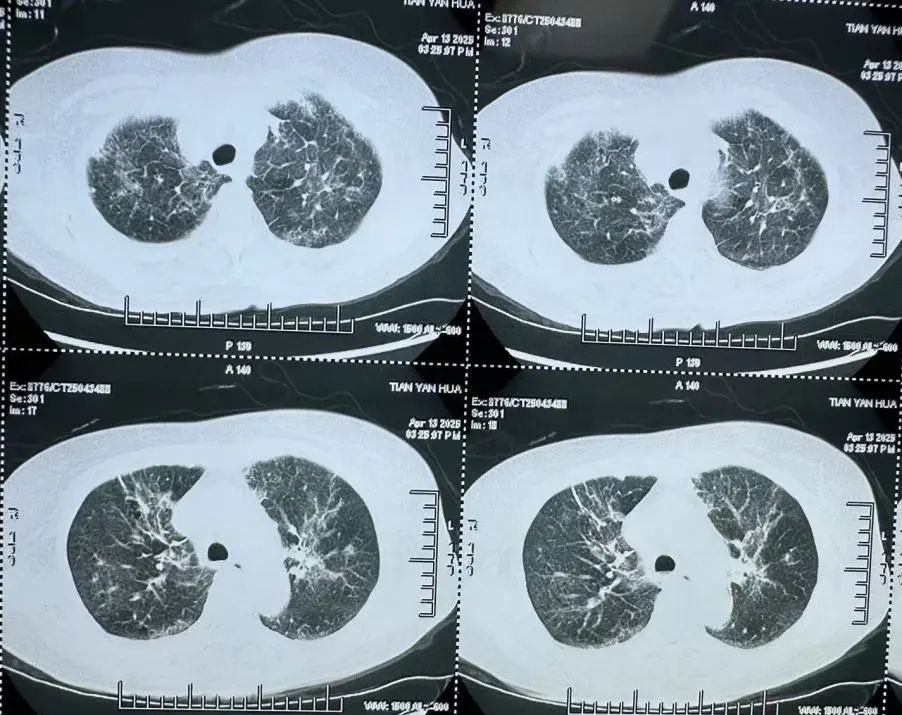

非HIV-PCP肺部影像

非HIV-PCP的早期癥狀與普通肺炎相似,但進展更快,48小時內(nèi)可能引發(fā)呼吸衰竭。有免疫缺陷病史(如腫瘤化療、器官移植、風濕免疫病長期用藥)等高危人群一旦出現(xiàn)持續(xù)發(fā)熱>1周,抗生素治療無效;干咳、進行性呼吸困難;血氧飽和度<93%等癥狀應立即到呼吸與危重癥醫(yī)學科就醫(yī),進行支氣管鏡肺泡灌洗檢查。